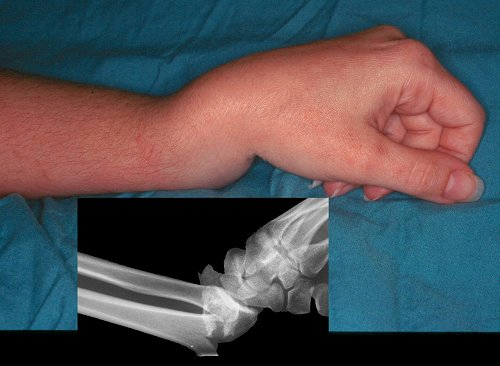

골절도 많이 물어보는 사람 많던데

쉽게 생각하면 이런식으로 누가봐도 눈으로 봤을때 뼈의 직접적인 변형이 관찰되면

KTAS 3등급이 된다. 이외는 4등급이라고 봐도 좋다.